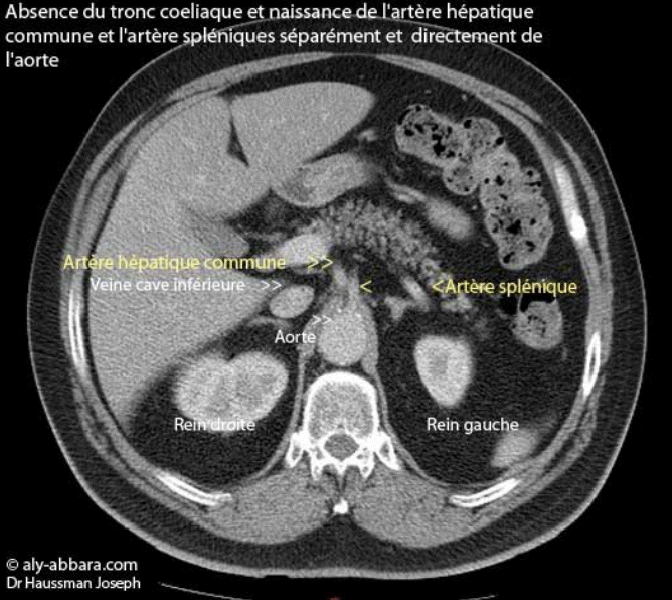

Image montrant l'absence du tronc coeliaque et la naissance de l'artère hépatique commune et l'artère splénique directement et séparément de l'aorte

Image montrant l'absence du tronc cœliaque et la naissance de l'artère hépatique

commune et l'artère splénique directement et séparément de l'aorte

(Scanner abdominal chez un individu âgé de 50 ans)

Habituellement, le tronc cœliaque naissant de l'aorte abdominale, se sépare en deux branches, la

branche droite, c'est l'artère hépatique commune, puis la branche gauche, c'est l'artère splénique.